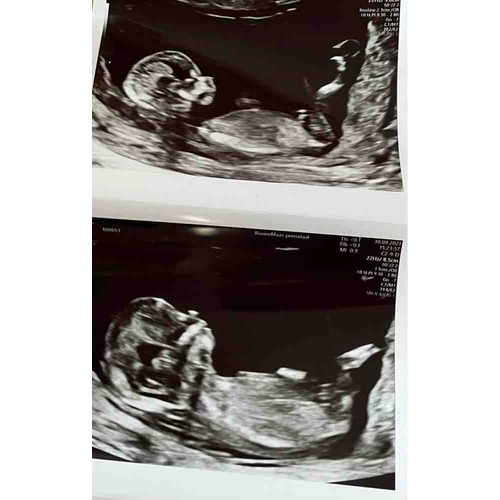

Daar zie je precies een piemeltje en een balletje, is mijn echo, weet ook nog niet 100% zeker maar dat maken ze mij wijs Hahaha 😅🙈

Staat inderdaad ook omhoog, dus een jongen!

Echt overduidelijk een jongen hoor haha! Onwijs leukkk❤️😍